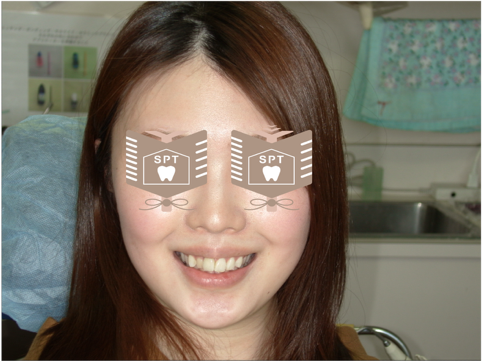

治療後の状態

被せた時の状態になります。やはり元々の歯の色が影響しているため、色が完全に一致しているかと言われば少し被せ物の方が黄色い印象になるかなぁって思います。間近で見るとそう思うのですが、顔貌写真や遠くから見ると全くわからない感じです。患者様に鏡や写真等で確認をしてもらい承諾していただきました。むしろ患者様は気にせず笑えるようになり嬉しいとまで言っていただくことができました。

この症例を通して感じたことは歯科医師が思う綺麗と患者様が思う綺麗は違うんだなぁって学ばせていただき、いかに患者様が納得していただくかが重要だと感じました。